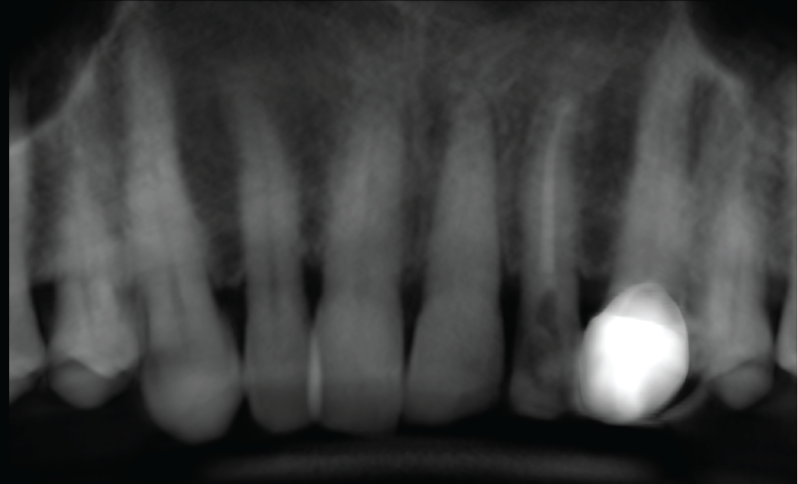

Findings:

The UL1 is displaced buccally with no root fracture. The apical vessels are likely torn due to the displacement. No alveolar fracture is seen, although there is a little buccal cortical plate still attached to the root of UL1.

CBCT Reconstructed Panoramic Image